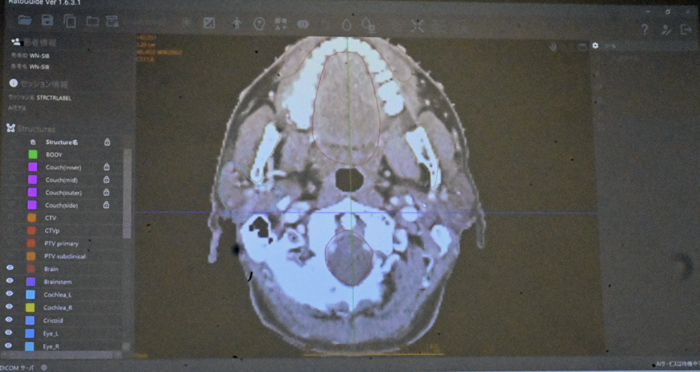

続いて、アイラトの角谷倫之・代表取締役が、同社が開発するAIを活用したIMRTの計画作成支援ソフト「RatoGuide(ラトガイド)」を紹介した。

IMRTは、コンピューターで放射線の照射角度や強度、形状などを細かく制御し、がんに集中して照射しながら正常組織への影響を抑える技術。治療効果は高い一方、綿密な照射計画を専門医が策定する必要があり、作成には時間もかかる。

「RatoGuide」は、IMRTの計画作成で、輪郭抽出や照射領域の決定、計画通りの線量が照射されるかを確認する安全性検証をAIが支援する。

東北大病院や山梨大学病院など協力関係にある大学病院から提供された90万件の治療データを読み込んでおり、一般的に約6時間かかる治療計画を、ソフトを使うことで20分程度に短縮できる。